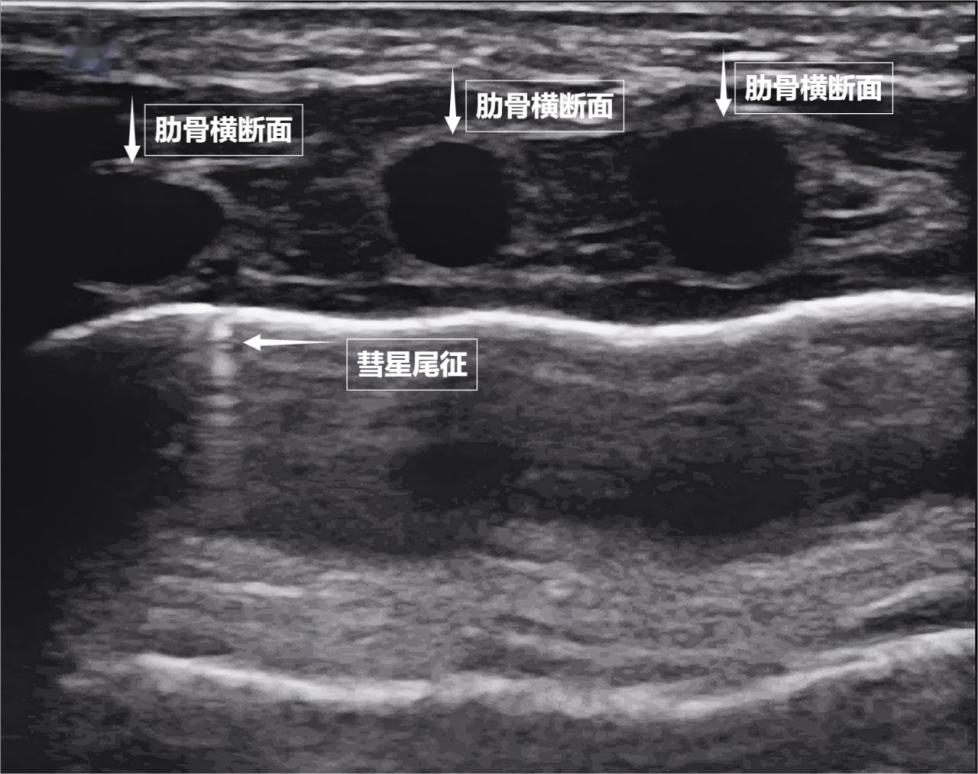

If we switch the ultrasound image to real-time dynamic mode, transforming a "photo" into a "movie," a more magical scene appears. As we breathe, the pleural line gently slides with the movement of the chest wall—this is the "lung sliding sign." It indicates that the lungs are closely attached to the chest wall, allowing for free and smooth breathing. If there is a pneumothorax or pleural effusion between the lungs and chest wall, this sliding disappears. Sometimes, tiny bright white flickering spots may also appear below the pleural line, known as the "comet tail sign" (see below). When they appear in small, isolated quantities, they are usually reflections of normal lung interlobular septa and are nothing to worry about.